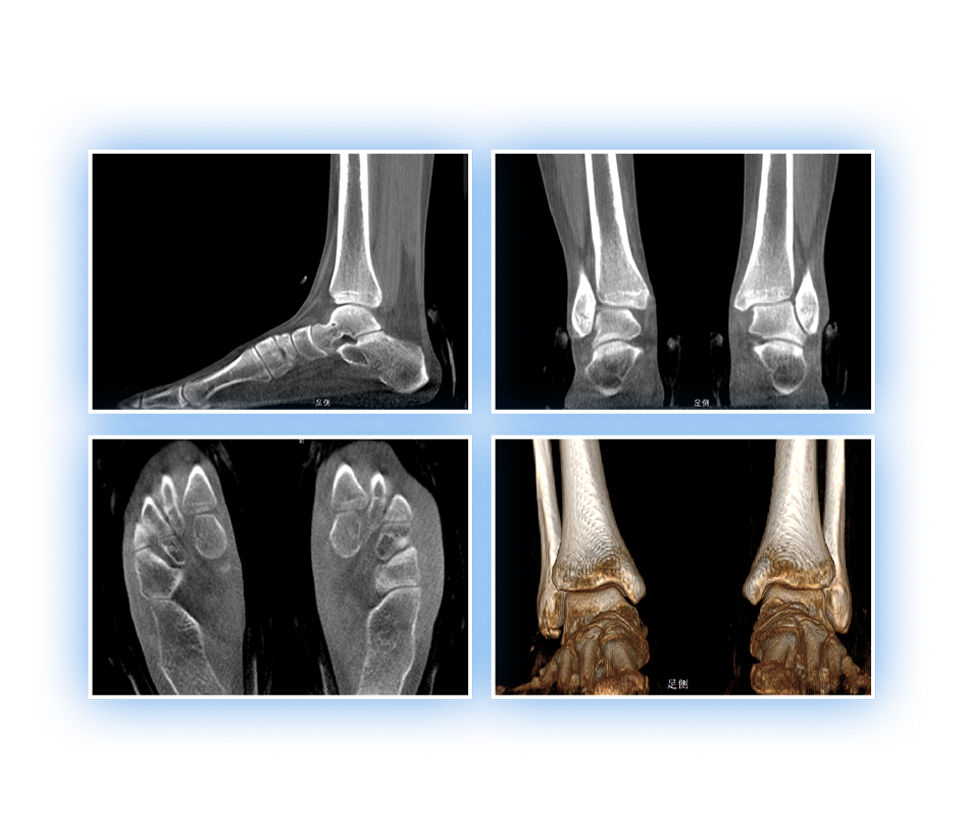

足踝

精準(zhǔn)診斷

手術(shù)方案規(guī)劃

術(shù)后隨訪(fǎng)